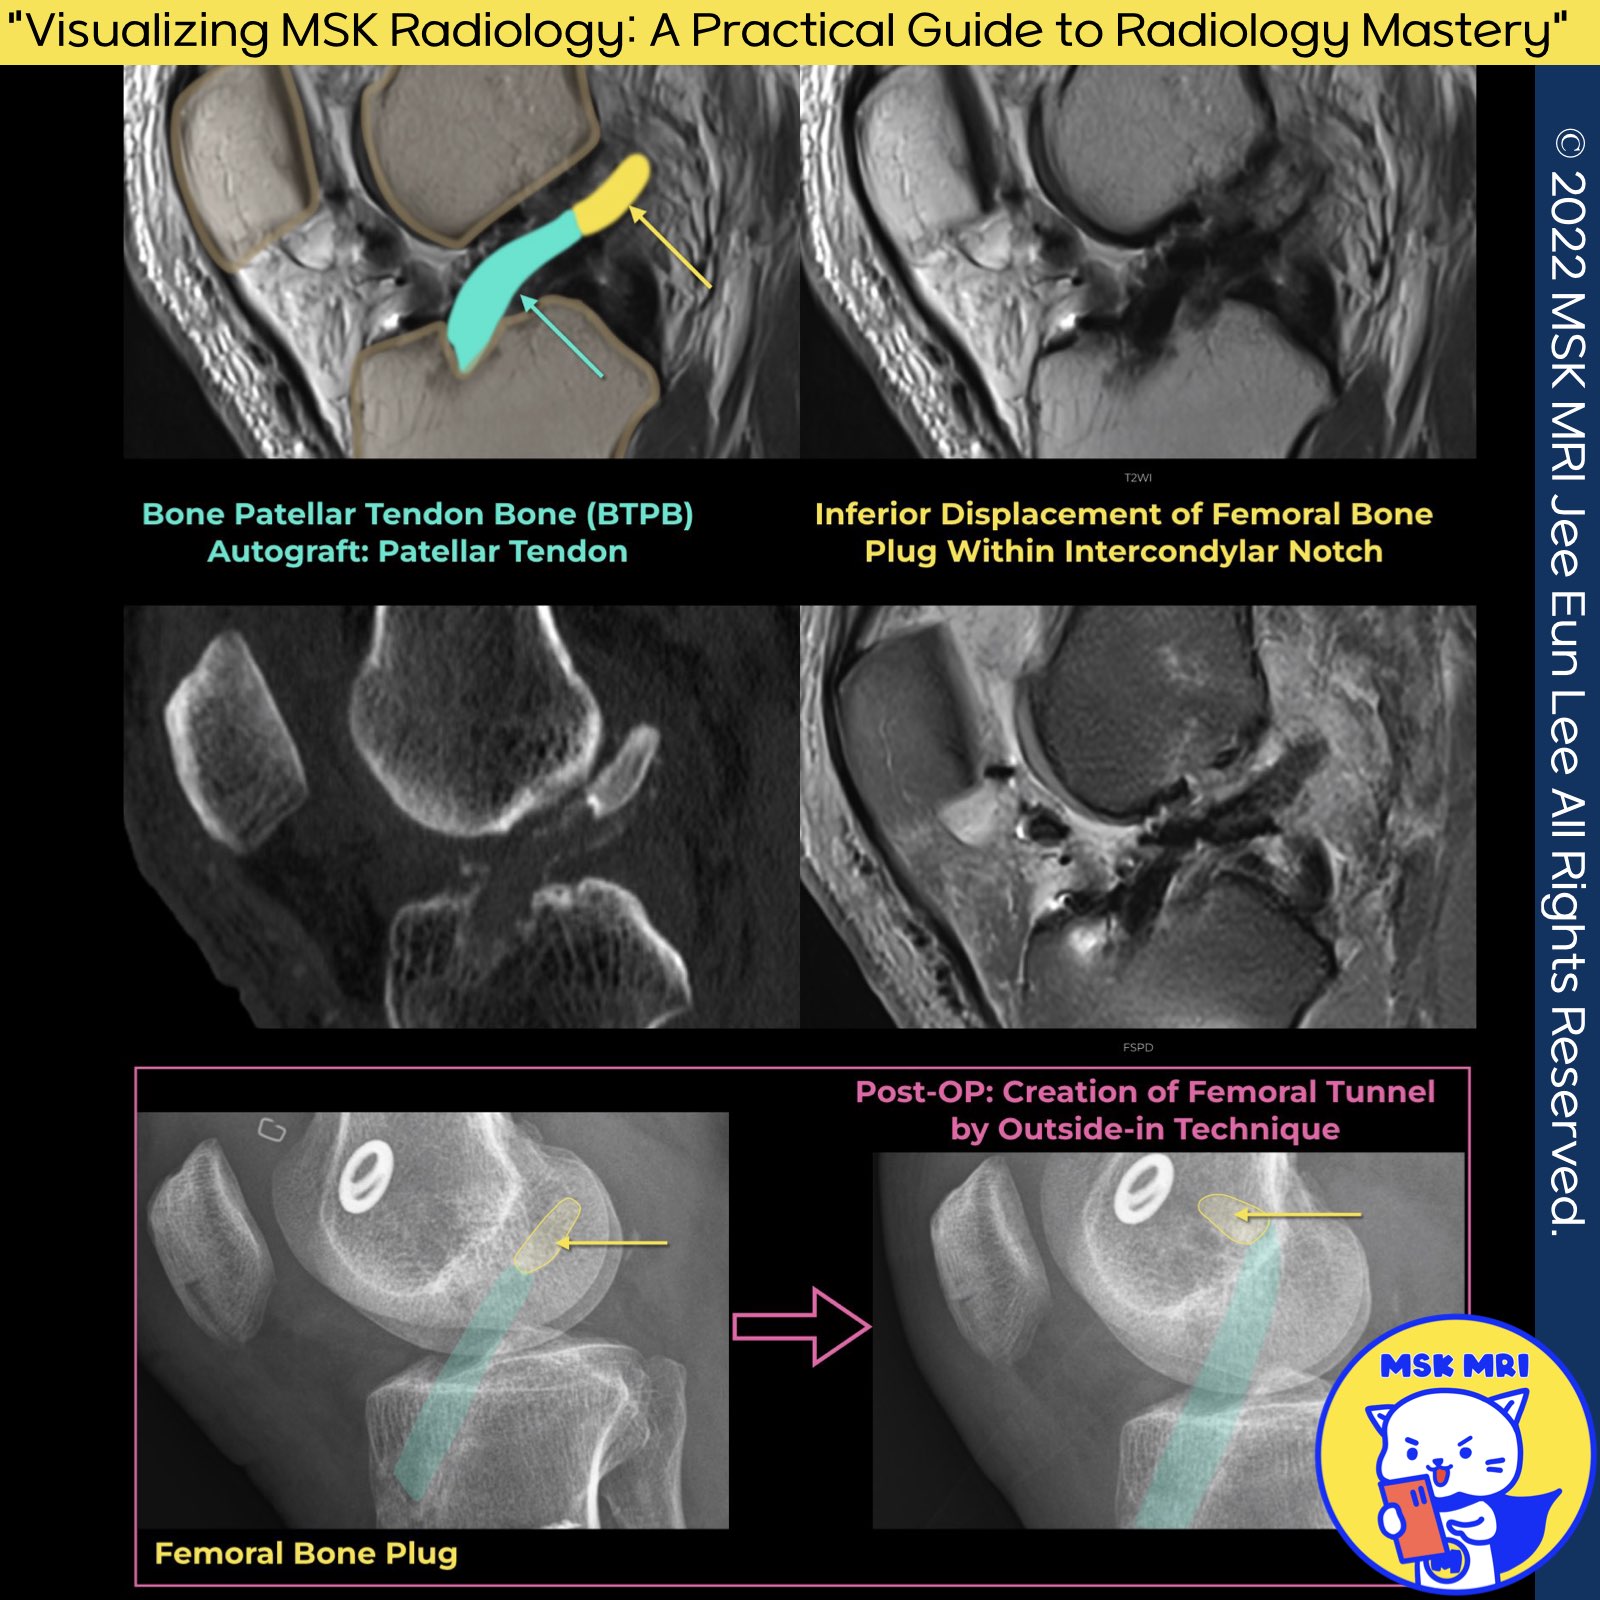

✅ Bone-Patellar Tendon-Bone (BPTB) Graft Bone Plug Migration

- BPTB graft complications in ACL reconstruction can include bone plug migration.

- Loose or dislodged screws can lead to bone plug migration.

- Even with an intact graft, the graft fails functionally if one end is not fixed.